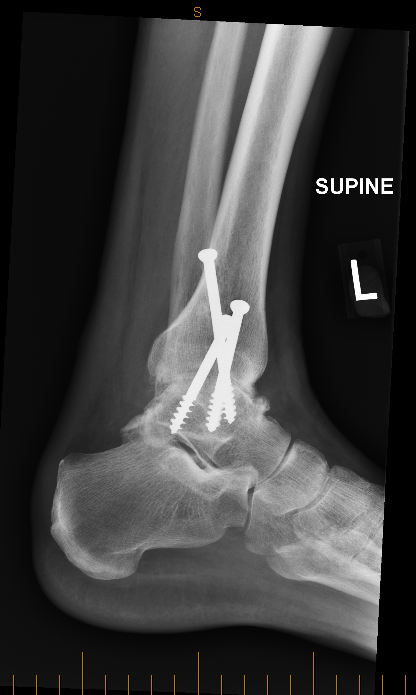

Rob is All Screwed Up 24/03/2022 / Robert / 1 Comment Six weeks in a cast now another six weeks in a moon-boot.